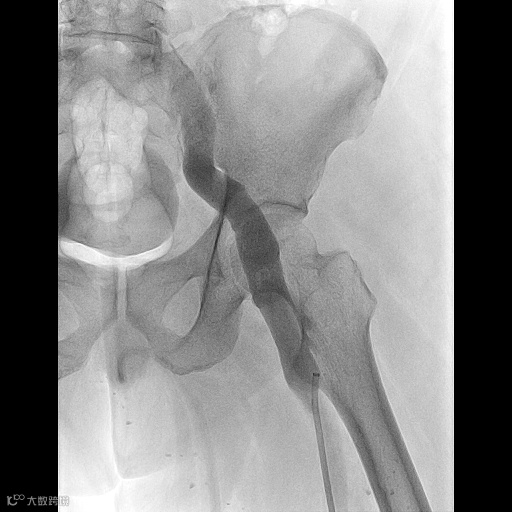

由沈阳市第一人民医院介入科陈建军主任团队运用中天天航™Pro血栓抽吸导管治疗一例急性左下肢深静脉血栓形成且伴有右下肢血流淤滞病变,成功清除血栓并快速恢复肢体灌注,欢迎大家阅读、分享、交流!

手术过程